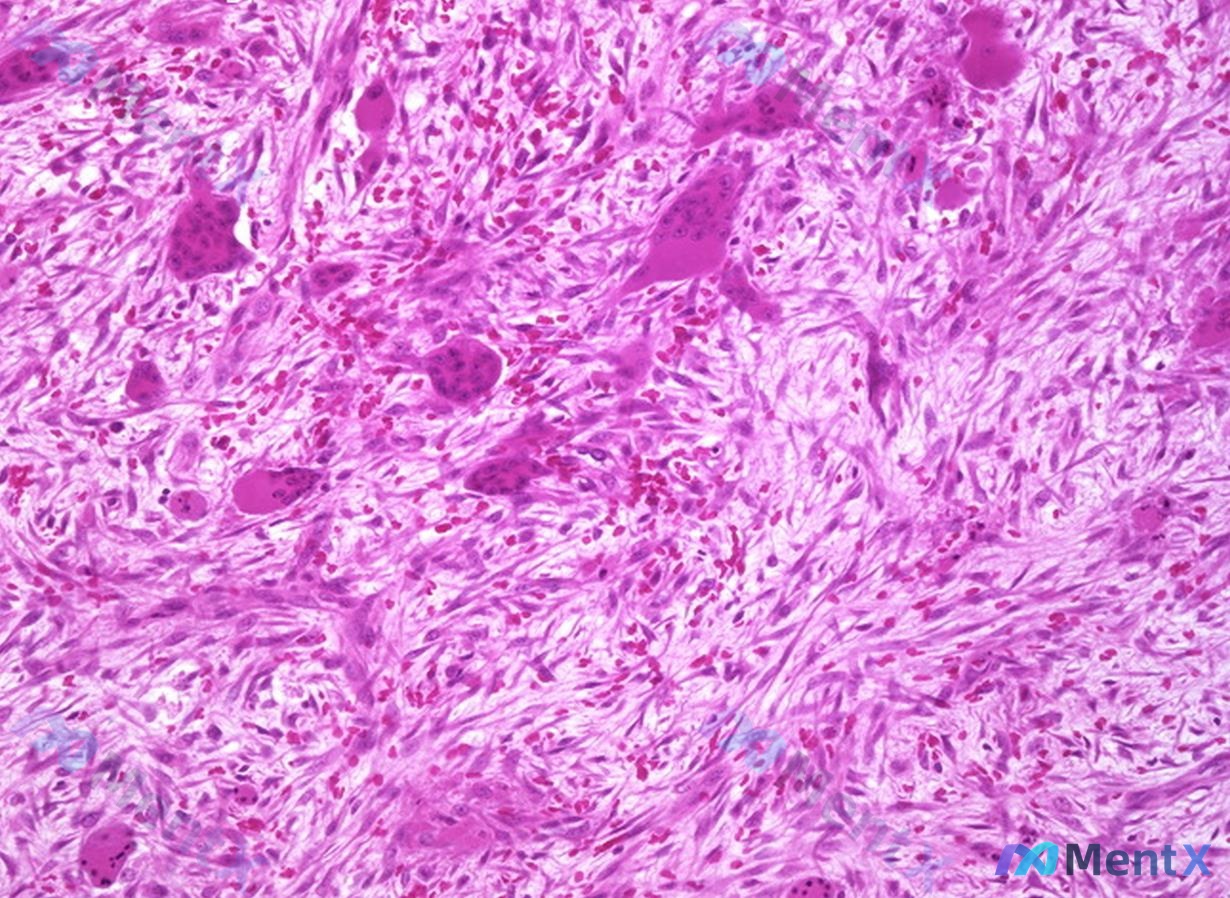

病理检查: - 骨组织显微镜下:大量梭形细胞增生,背景中散布大量多核巨细胞。骨小梁不规则碎裂,周围纤维结缔组织包绕,伴出血及含铁血黄素沉积。未见明显核异型性或核分裂象。